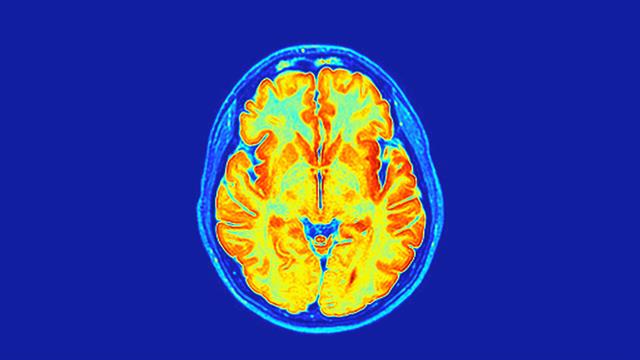

Ερευνητές του Griffith University χρησιμοποίησαν εξελιγμένες τεχνικές MRI για να αξιολογήσουν τις νευρολογικές επιπτώσεις της  COVID-19 σε σύγκριση με ανθρώπους που δεν μολύνθηκαν ποτέ.

Ο Dr. Kiran Thapaliya, είπε ότι οι ερευνητές εξέτασαν τη λευκή και φαιά ουσία, περιοχές που είναι ζωτικής σημασίας για τη μνήμη, τις γνωστικές ικανότητες και τη γενική υγεία του εγκεφάλου και ανακάλυψαν σαφείς διαφορές.

Η μοναδική μέθοδος μαγνητικής τομογραφίας εντόπισε σημαντικές αλλαγές σε νευροχημικές ουσίες του εγκεφάλου, στην ένταση του εγκεφαλικού σήματος και στη δομή των ιστών σε ανθρώπους με Long COVID αλλά και σε αυτούς που θεωρούσαν ότι είχαν αναρρώσει πλήρως.

Η μελέτη ανέφερε επίσης ότι αλλαγές στον ιστό του εγκεφάλου συνδέονταν με την ένταση των συμπτωμάτων σε ανθρώπους με Long COVID, υποδεικνύοντας ότι ο ιός μπορεί ενδεχομένως να αφήσει σιωπηλή, διαρκείας επίδραση στην υγεία του εγκεφάλου.